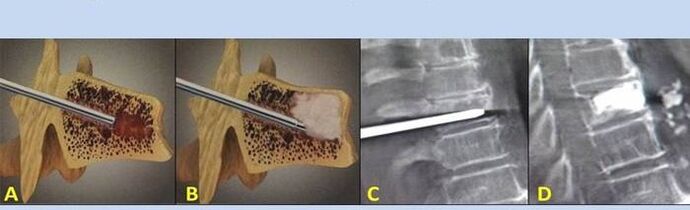

- Nucleoplastia – Eliminación do núcleo do disco. A operación alivia a presión sobre as terminacións nerviosas.

- Vertebroplastia de punción – Método de estabilización das vértebras. Durante o procedemento, o médico enche as cavidades da columna con cemento óseo.